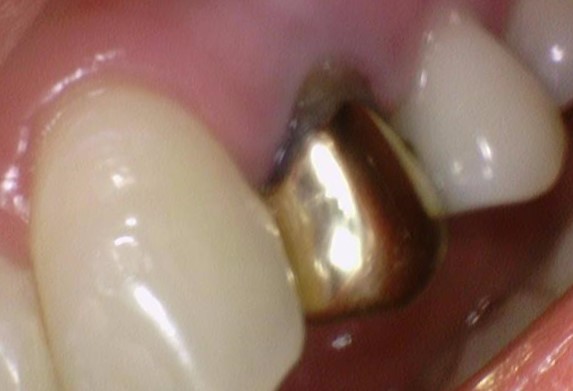

![[서울역/광화문] 오래된 크라운에 음식물이 많이 껴요 →해결방법은? 관련 이미지 4](https://pub-9f2bb3498faf4d1d8714b41df24753e3.r2.dev/content/clinics/archive/rseeanjxfu/naver_blog/yonseiyegam/assets/by_hash/94791a2e6c21b22dbdaa1077cd0f844034d55bae47d098b3126246a9776d9385.jpg)

오래된 금 크라운(왼쪽사진), 금크라운을 뜯은 상태(오른쪽 사진)